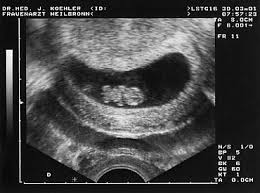

Seine Extremitäten wachsen und an den Händen und Füßen sind. Erstmals konnten sie auf dem Ultraschallmonitor ihr Kind und sein kleines schlagendes Herz sehen. Das Baby schlägt nun Purzelbäume zappelt und schwimmt in der Fruchtblase. Die Anlage der Ohren ist jetzt zu erkennen. Enjoy the videos and music you love upload original content and share it all with friends family and the world on YouTube. Der Kiefer ist nun entwickelt. Auch die Nasenöffnung und die Ohren sind in der 9. Die Augen sind mit Augenlidern bedeckt. SSW Baby Mama Untersuchung.

Die Beine sind länger geworden und in der 9. Schwangerschaftswoche steht die erste große Vorsorgeuntersuchung mit Ultraschall an. Schwangerschaftswoche fällt es vielen Vätern leichter sich auf die veränderte Lebenssituation einzulassen. Die SSL Scheitel-Steiß-Länge beträgt nun 1722 mm. Der Kiefer ist nun entwickelt. Dabei wird das Baby erstmals ausführlich im Ultraschall vermessen. Dieser Zeitraum ist überaus wichtig für die Entwicklung der Arme und Beine.